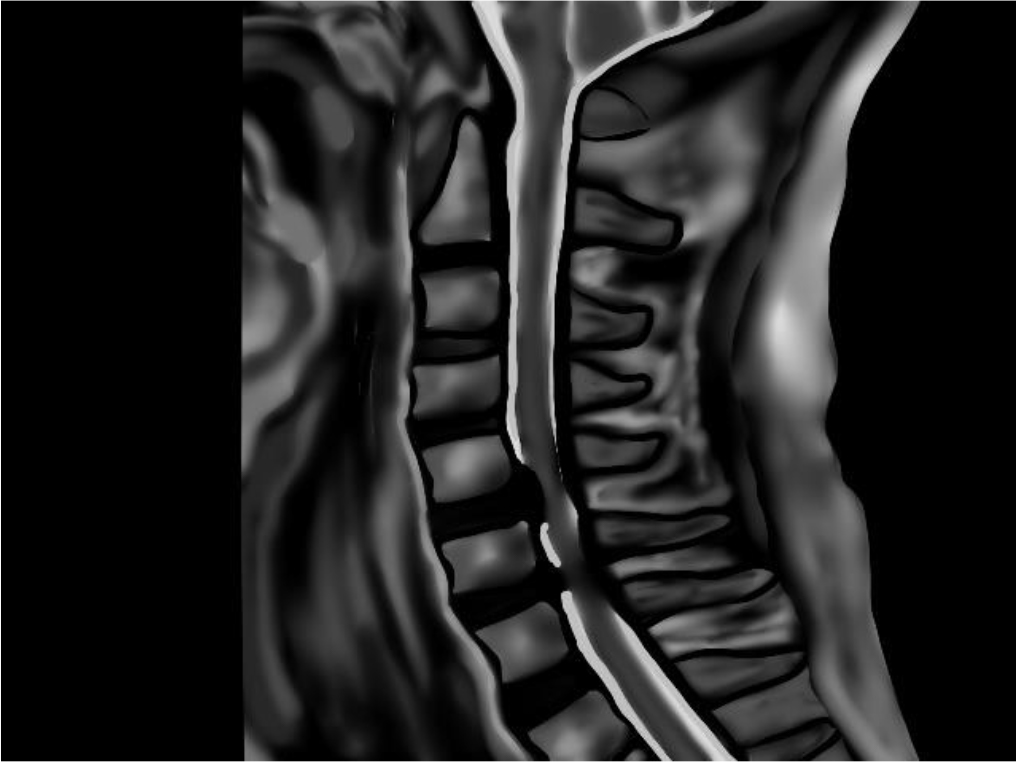

■頚椎症性脊髄症

加齢による椎間板の変性が進み、骨がとげ状に大きくなって骨棘を形成することや、靭帯が厚く硬くなることで脊柱管にある脊髄が圧迫され、四肢に痛み、しびれが出る疾患です。

■頸椎椎間板ヘルニア

頸椎を構成する椎骨と椎骨の間には椎間板というクッション性のある組織が存在します。何らかの原因でその椎間板が飛び出し、神経を圧迫するのが椎間板ヘルニアです。

■頚部脊柱管狭窄症

主に加齢に伴う椎間板の変性により、劣化・膨隆・突出、黄色靭帯の肥厚が原因となり、それらによって脊髄や神経根が脊柱管を狭窄します。その結果、神経の血流が低下して神経障害を起こした状態をいいます。

長期的(3か月)以上続く首の痛み・コリの場合は、まず病院で適正な検査を受けることをおすすめします。そして内科疾患以外のものは整形外科へ行くことをすすめます。レントゲン、MRI 、血液検査を行えば、大抵の原因がわかるはずです。また検査をしても原因が分からない痛みや症状は当院は得意としています。